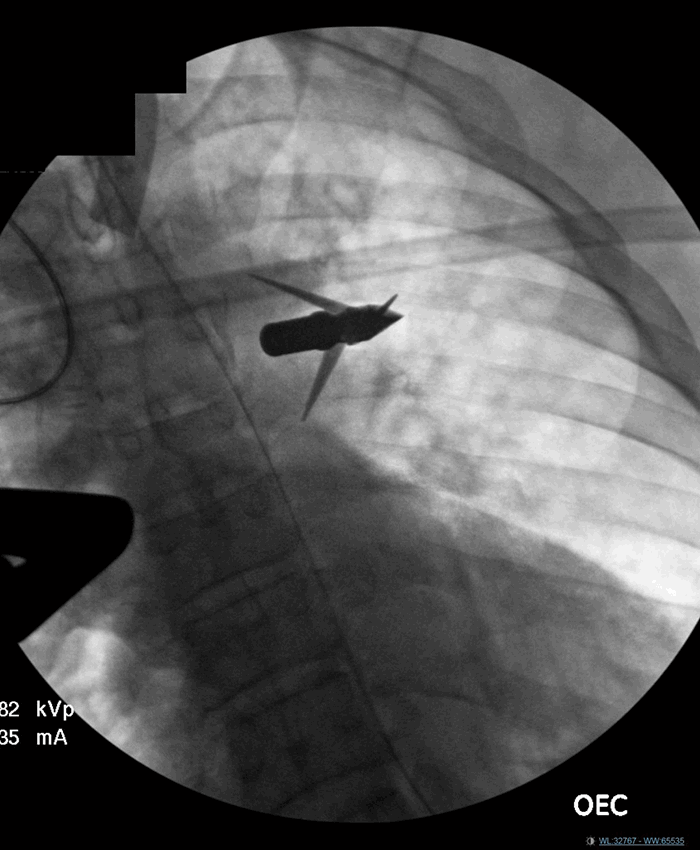

On arrival to the ED, the patient had absent right-sided breath sounds and was hypotensive. Urgent needle decompression was performed followed by placement of a 28 French chest tube with evacuation of 550 mL blood. Massive transfusion protocols were initiated. Primary trauma survey was significant for bilateral lower extremity paralysis. In addition to the penetrating wound to his right anterior chest, he also had a palpable foreign body in the subcutaneous tissue posteriorly in his left upper back near his spinal cord. Chest x-ray was significant for metallic foreign bodies near the aortic arch and a widened mediastinum (Figure 1). Focused assessment with sonography for trauma (FAST) exam was negative for cardiac tamponade. The patient continued to remain hypotensive and was taken emergently to the operating room for an open right thoracotomy.

Figure 1. AP supine chest x-ray of a 51-year-old man upon arrival to the trauma bay with a penetrating arrow thoracic injury